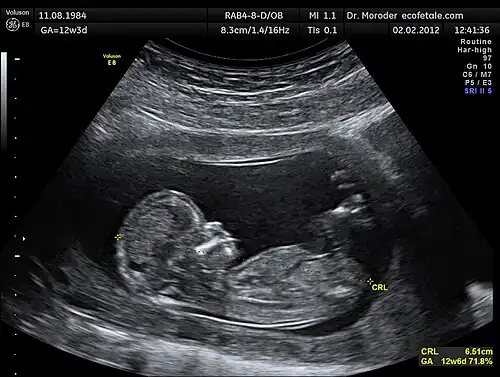

Modern ultrasonography use arrays of small transducers, each of which are individually electronically controlled to achieve an effect know as beamforming. When using this technique, control of the phase relation between array elements results in control over the emitted beam's direction and focal depth.[7] To produce a two-dimensional ultrasound image, the ultrasound beam focal position is swept through a region, and the recorded reflected waves are correlated to the particular focal locations. The exact process by which this general concept is accomplished varies with each ultrasonography instrument. Figure 1 provides a sample 2D image produced by the sweeping of the focal location through a 2D plane.